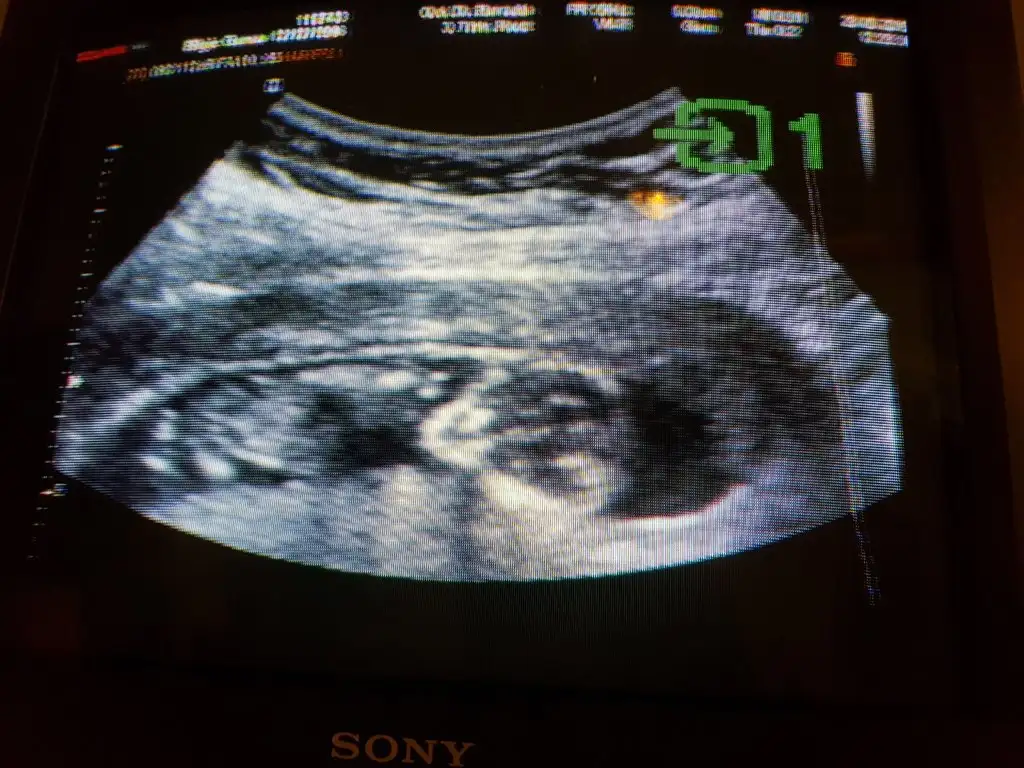

Keseye bakılırsa kız.

Pozisyona bakılırsa, erkek.

Ben erkek diyorum kesenin istisna oluşundan ötürü.

Benimde 12 haftalik merak ettim tahmininiz nedir?